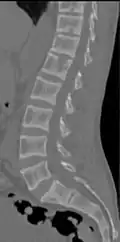

Renal osteodystrophy is usually diagnosed after treatment for end-stage kidney disease begins; however the CKD-MBD starts early in the course of CKD.[1][6] In advanced stages, blood tests will indicate decreased calcium and calcitriol (vitamin D) and increased phosphate, and parathyroid hormone levels. In earlier stages, serum calcium, phosphate levels are normal at the expense of high parathyroid hormone and fibroblast growth factor-23 levels. X-rays will also show bone features of renal osteodystrophy (subperiostic bone resorption, chondrocalcinosis at the knees and pubic symphysis, osteopenia and bone fractures) but may be difficult to differentiate from other conditions. Since the diagnosis of these bone abnormalities cannot be obtained correctly by clinical, biochemical, and imaging methods (including measurement of bone-mineral density), bone biopsy has been, and still remains, the gold standard analysis for assessing the exact type of renal osteodystrophy.[6][16]